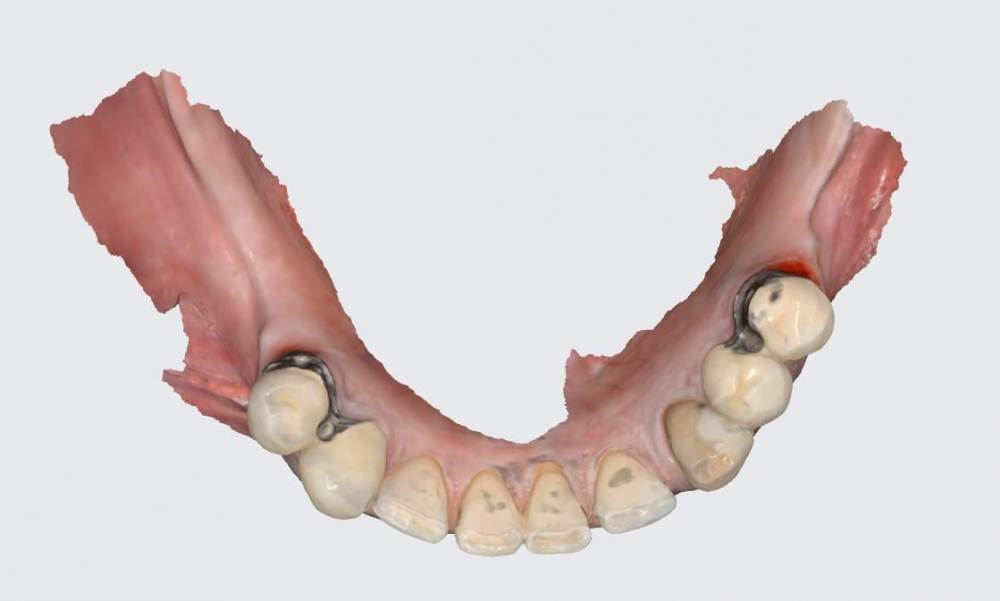

АнтонТЛТ Опубликовано 26 июня, 2023 Поделиться Опубликовано 26 июня, 2023 Техник сканировал основания и делал как цементные коронки с дыркой? Ссылка на комментарий

karasov Опубликовано 26 июня, 2023 Автор Поделиться Опубликовано 26 июня, 2023 25 минут назад, АнтонТЛТ сказал: Техник сканировал основания и делал как цементные коронки с дыркой? да Ссылка на комментарий